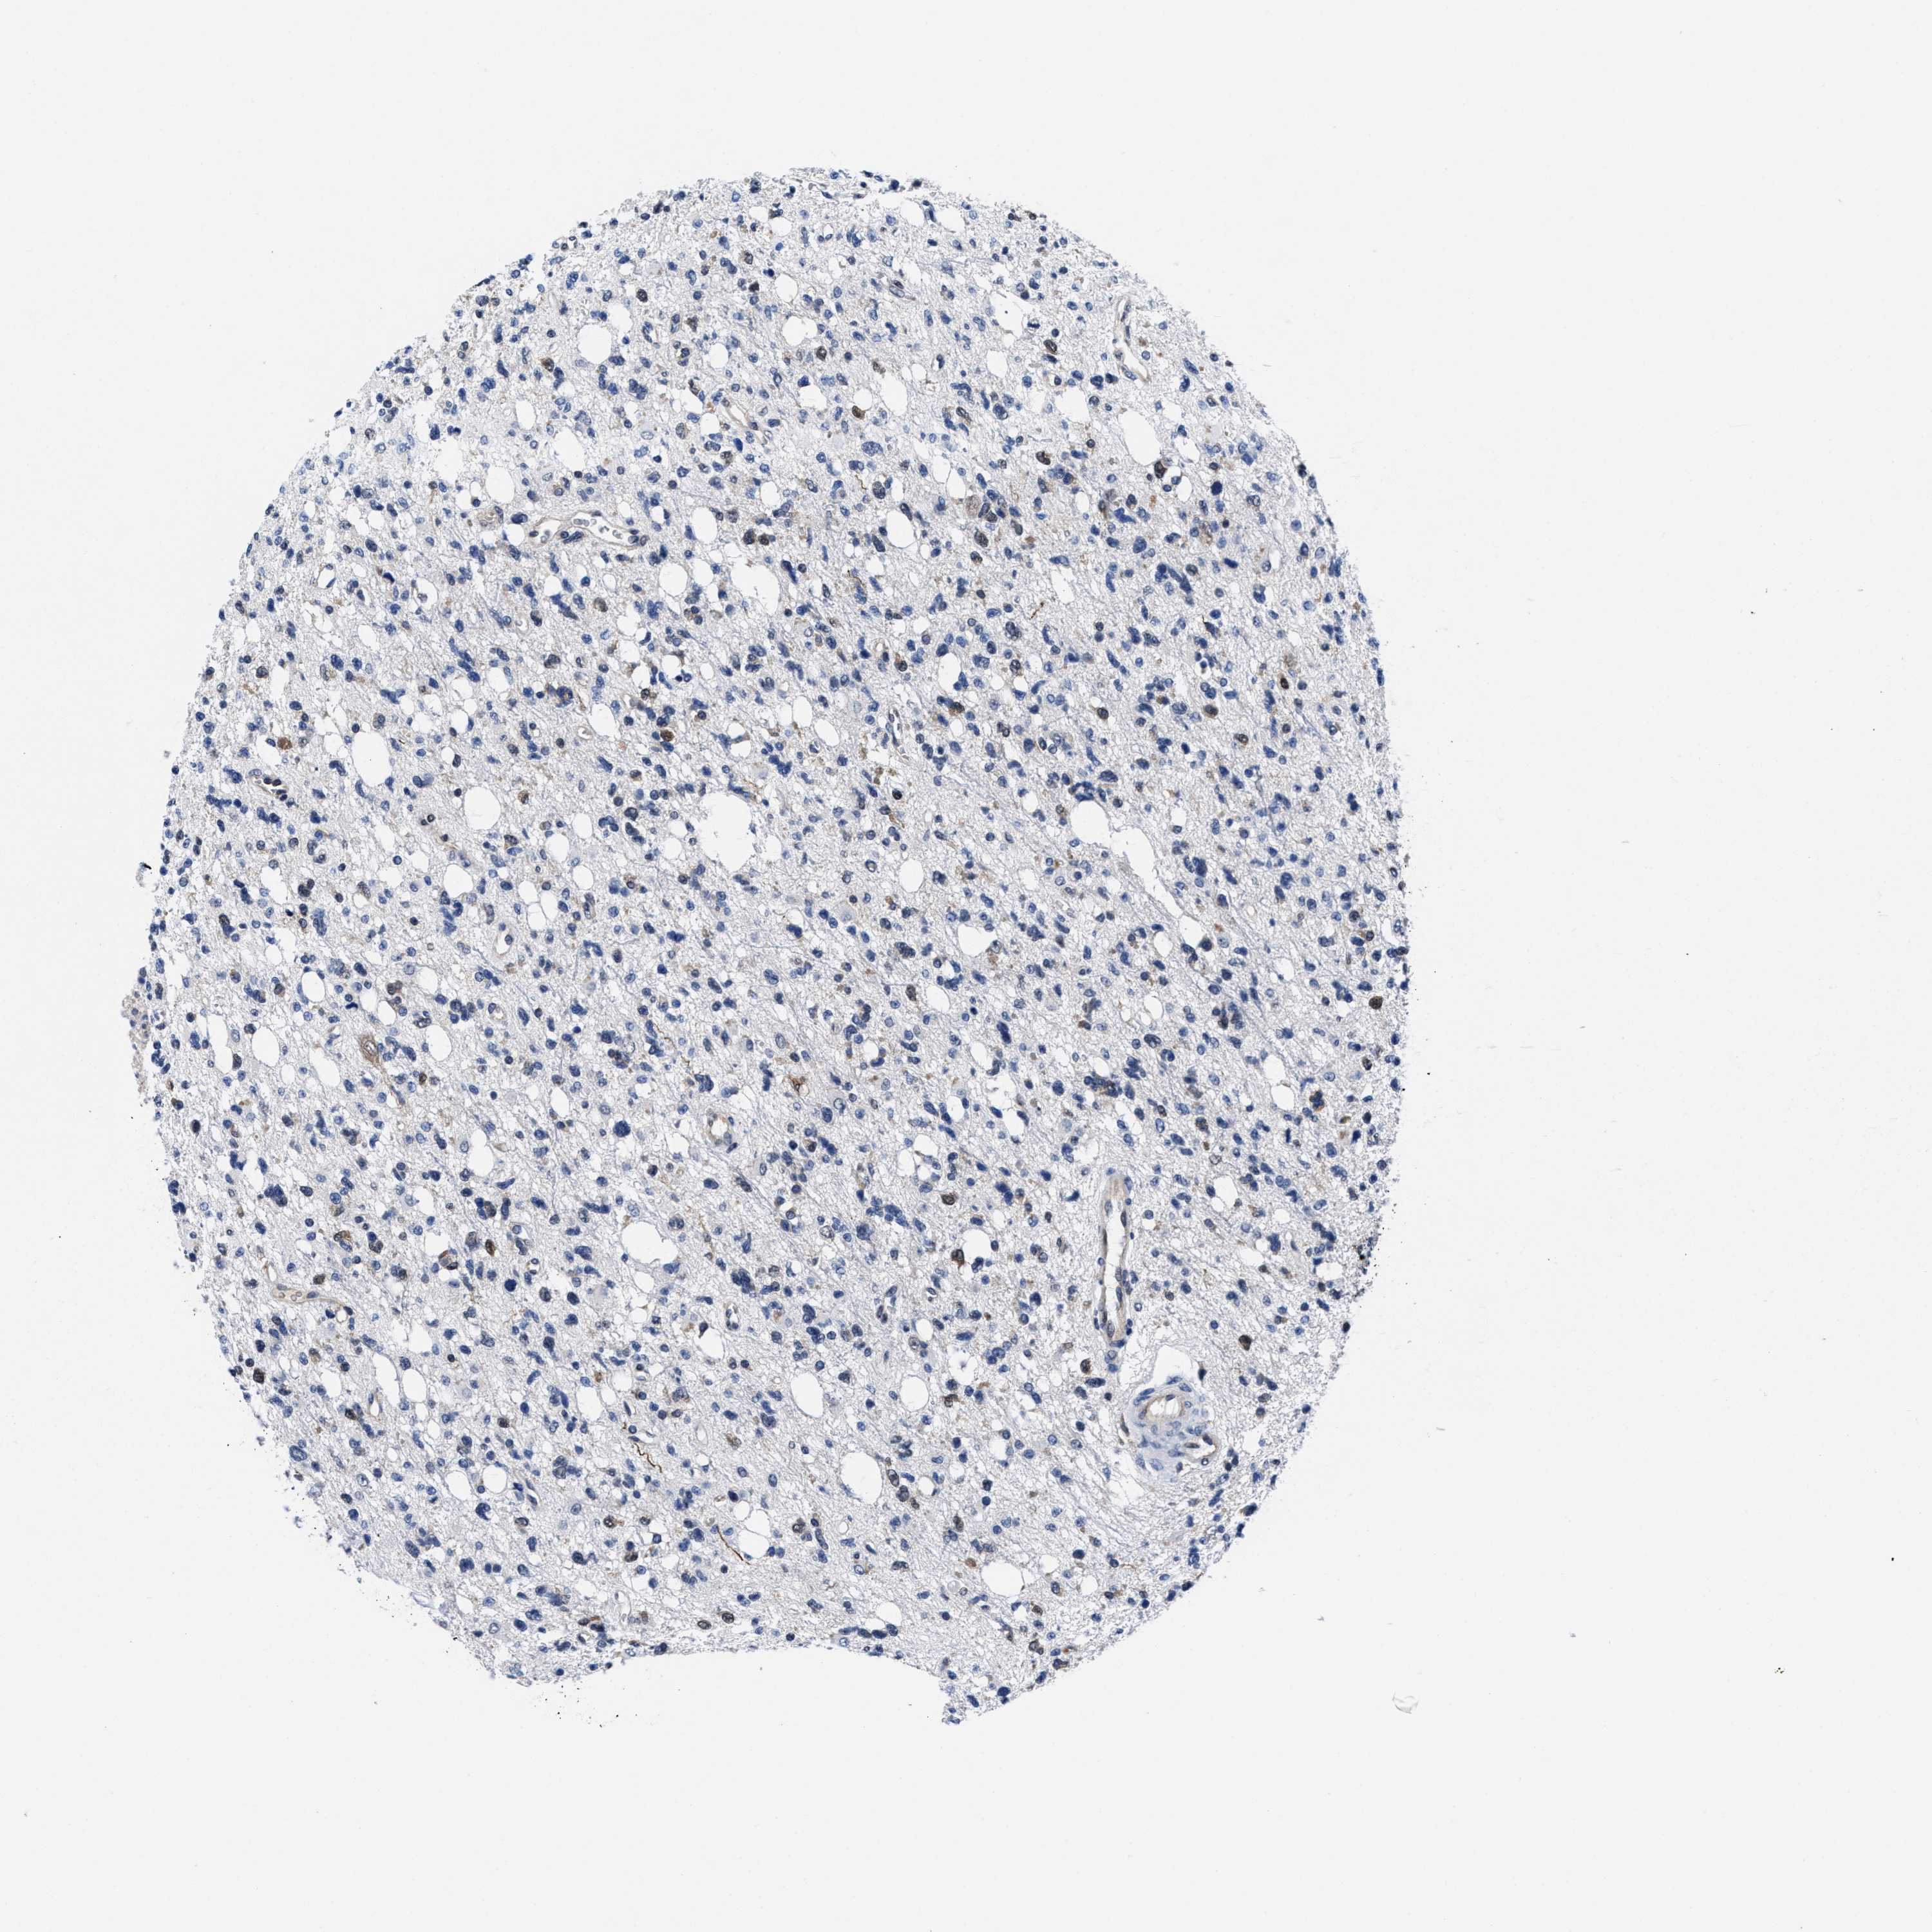

GLIOMA - Protein expressioni

A mouse-over function shows sample information and annotation data. Click on an image to view it in a full screen mode. Samples can be filtered based on level of antibody staining by selecting one or several of the following categories: high, medium, low and not detected. The assay and annotation is described here.

Note that samples used for immunohistochemistry by the Human Protein Atlas do not correspond to samples in the TCGA dataset.

Antibody stainingi

Antibody staining in the annotated cell types in the current human tissue is reported as not detected, low, medium, or high, based on conventional immunohistochemistry profiling in selected tissues. This score is based on the combination of the staining intensity and fraction of stained cells.

Each image is clickable and will lead to virtual microscopy that enables deeper exploration of all samples and also displays staining intensity scores, fraction scores and subcellular localization as well as patient and tissue information for each sample.

HPA022434

HPA022953

HPA022959

HPA028758

CAB007783

Glioma, malignant, High grade

Glioma, malignant, Low grade

Glioblastoma, NOS